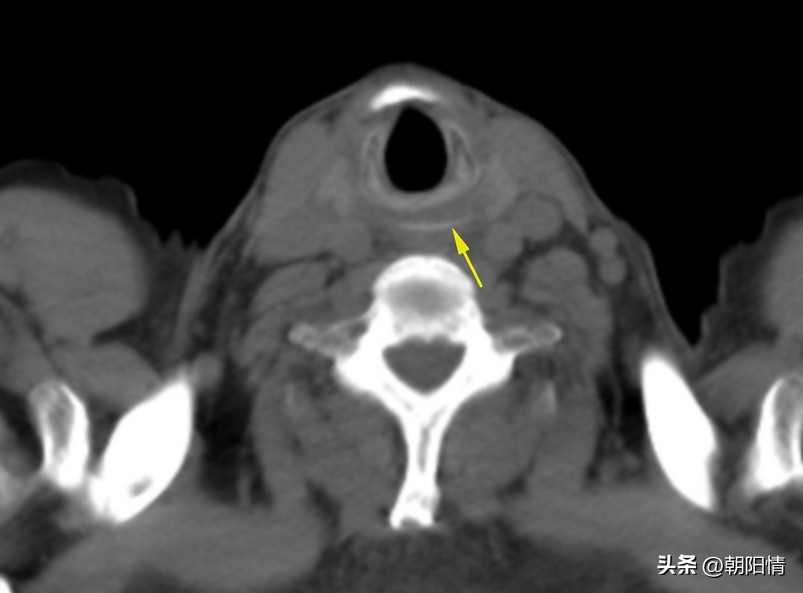

(1)颈段食管异物

Case2:食管环状软骨水平异物(鱼骨)。

随着多层螺旋CT的发展及其重建技术的应用,多层螺旋CT可以明确消化道异物的诊断,了解异物的大小、形态及异物与周围组织的关系,观察食管、肠管周围是否存在并发症。为临床提供丰富的诊疗信息,具有重要的参考价值。